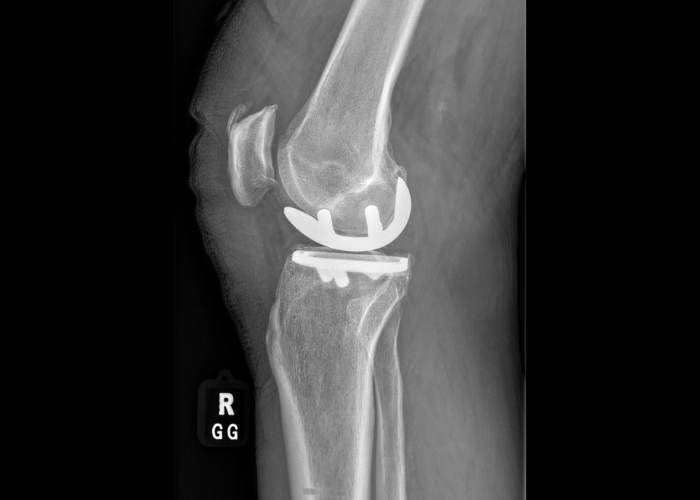

What Is a Medial Partial Knee Replacement?

A medial partial knee replacement focuses on the inner (medial) compartment of the knee, the area most commonly affected by arthritis. Rather than resurfacing the entire joint, the procedure targets only the worn portion while leaving the unaffected structures like the ACL, PCL, MCL, and unaffected bone and cartilage intact. By maintaining the knee’s normal ligaments and healthy areas, this approach can provide more natural movement, a faster recovery, and strong functional outcomes in carefully selected patients. Moreover, minimal balancing is required which generally eliminates the concern for an unstable, loose, or tight knee after surgery.

You may be a candidate for a medial partial knee replacement if you have pain primarily on the inside of the knee. Pain of this type can often be associated with bow-leg alignment (varus knee). This condition is typically confirmed through X-rays showing cartilage wear limited to the medial compartment, while the rest of the knee remains relatively healthy. An MRI is not always helpful in determining candidacy as Dr. Ramkumar relies on your exam, carefully inspects your standing x-rays, and leaves the final decision to proceed with a partial to intraoperative inspection of the surrounding knee compartments at the time of surgery.